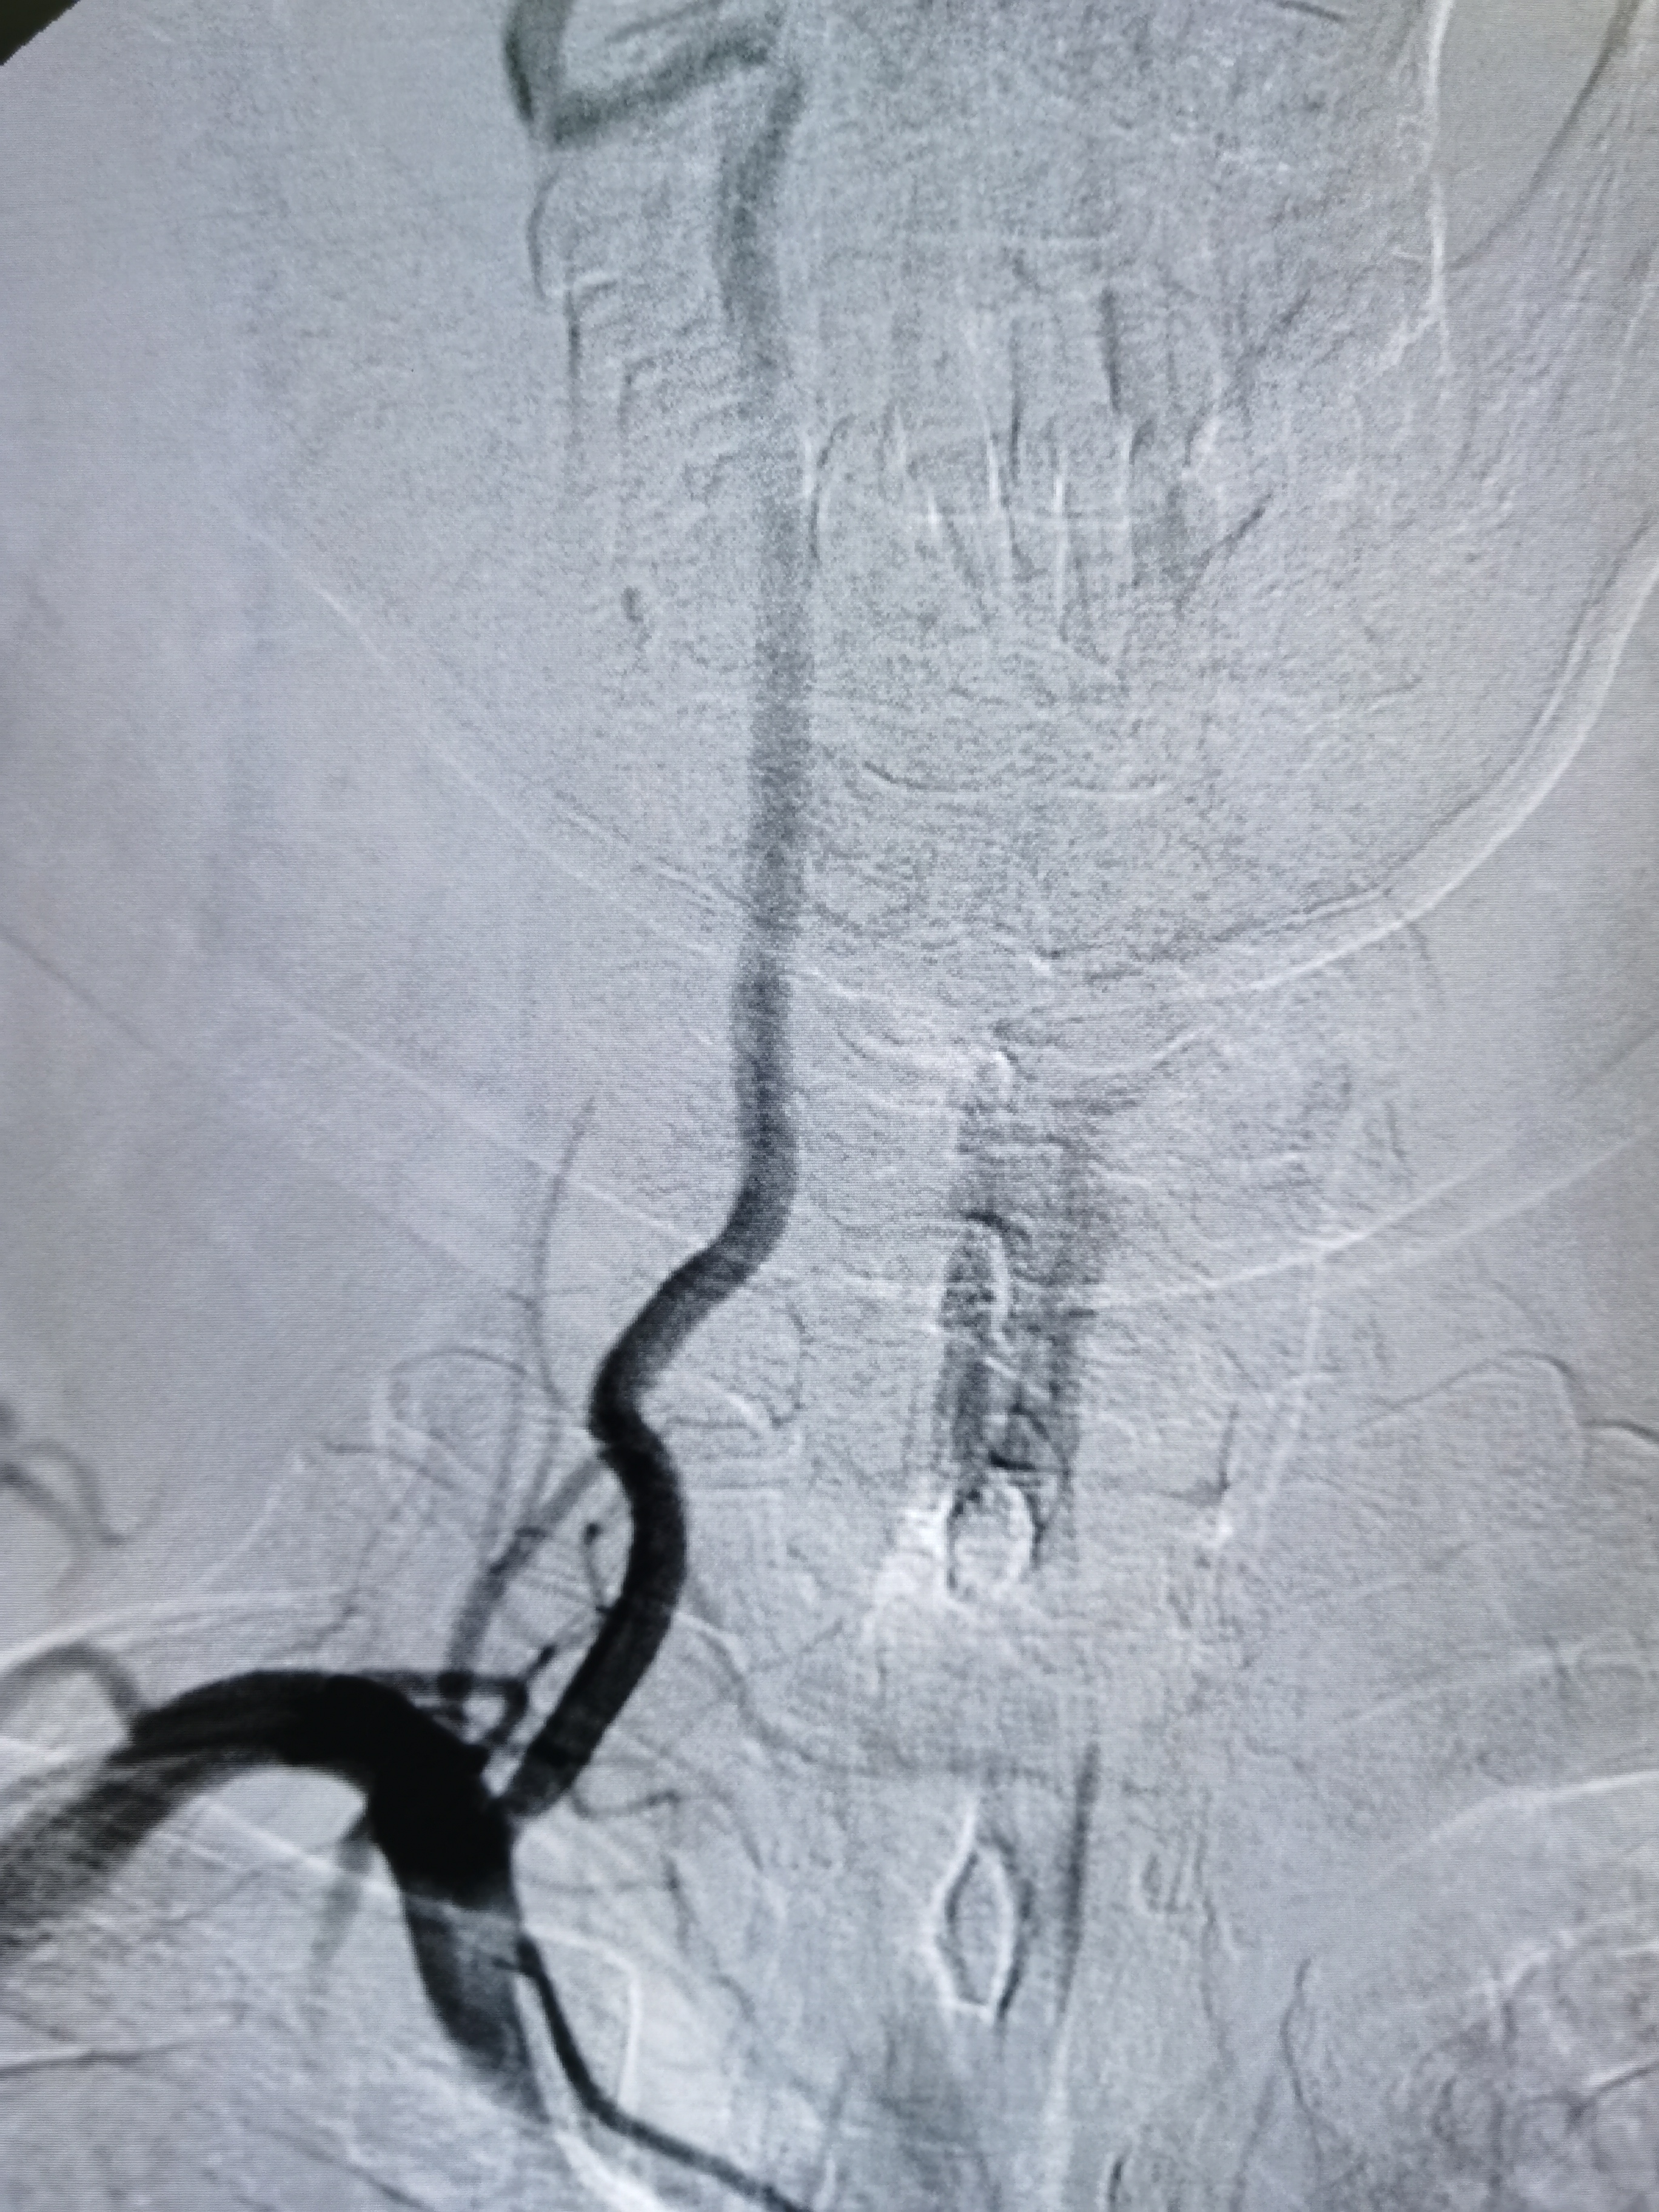

将8F导引导管送至左侧锁骨下动脉近左椎动脉起始部,微导丝顺利通过病变,2.0/20球囊预扩病变。

3、手术过程中,先用小球囊扩张病变,观察血栓情况,及时应用支架全程覆盖血栓及病变部位,成形满意。